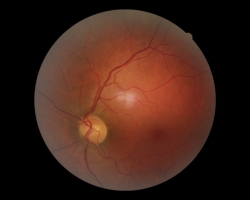

- OD : discret œdème papillaire avec surtout une pâleur papillaire car cliché pris > 1 mois après début des symptômes. L’œdème est en fait en régression et évoluera à terme vers une atrophie optique sectorielle supérieure

- OG : aspect normal

FO : cf. images jointes